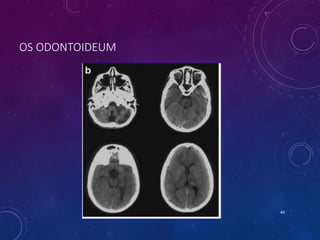

OS ODONTOIDEUM

• Failure of basal dental and axis body ossification centers to fuse at LS.

• Non-fusion is below the level of transatlantal lig - a/w instability.

• Orthotopic and dystopic (Os avis).

• Radiographic features:

• Smooth, well-corticated ossicle at the superior ossicle of a hypoplastic dens

• around half the size of a normal dens

• a/w hypertrophied and rounded anterior arch of the atlas

• Posterior arch is hypoplastic

43

• #44 D/d: Odontoid fracture type 2 Persistent ossiculum terminale